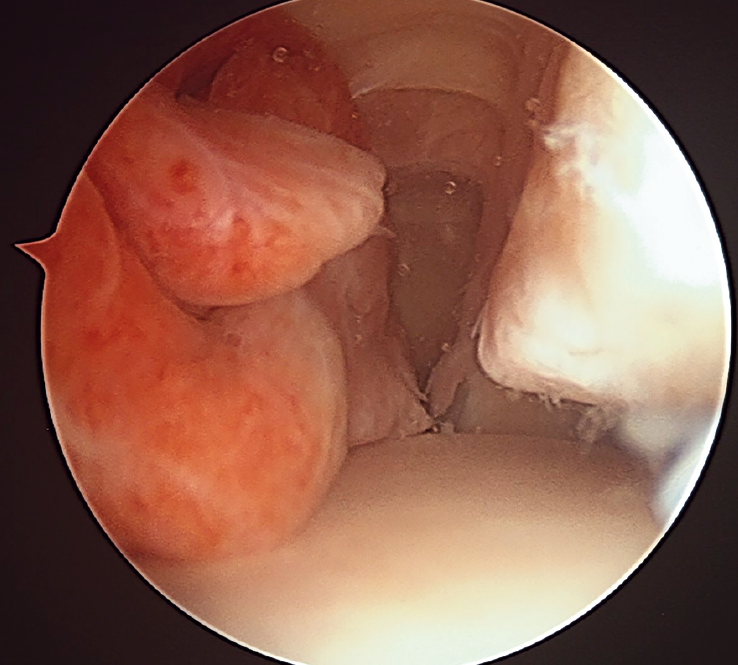

View from the arthroscopic anteromedial portal of the right ankle in lateral direction: a mammillated and hyperemic mass is observed, corresponding to pigmented villonodular synovitis in the anterior compartment of the ankle, causing a spatial conflict between the dome of the astragalus and the anterodistal border of the tibia.